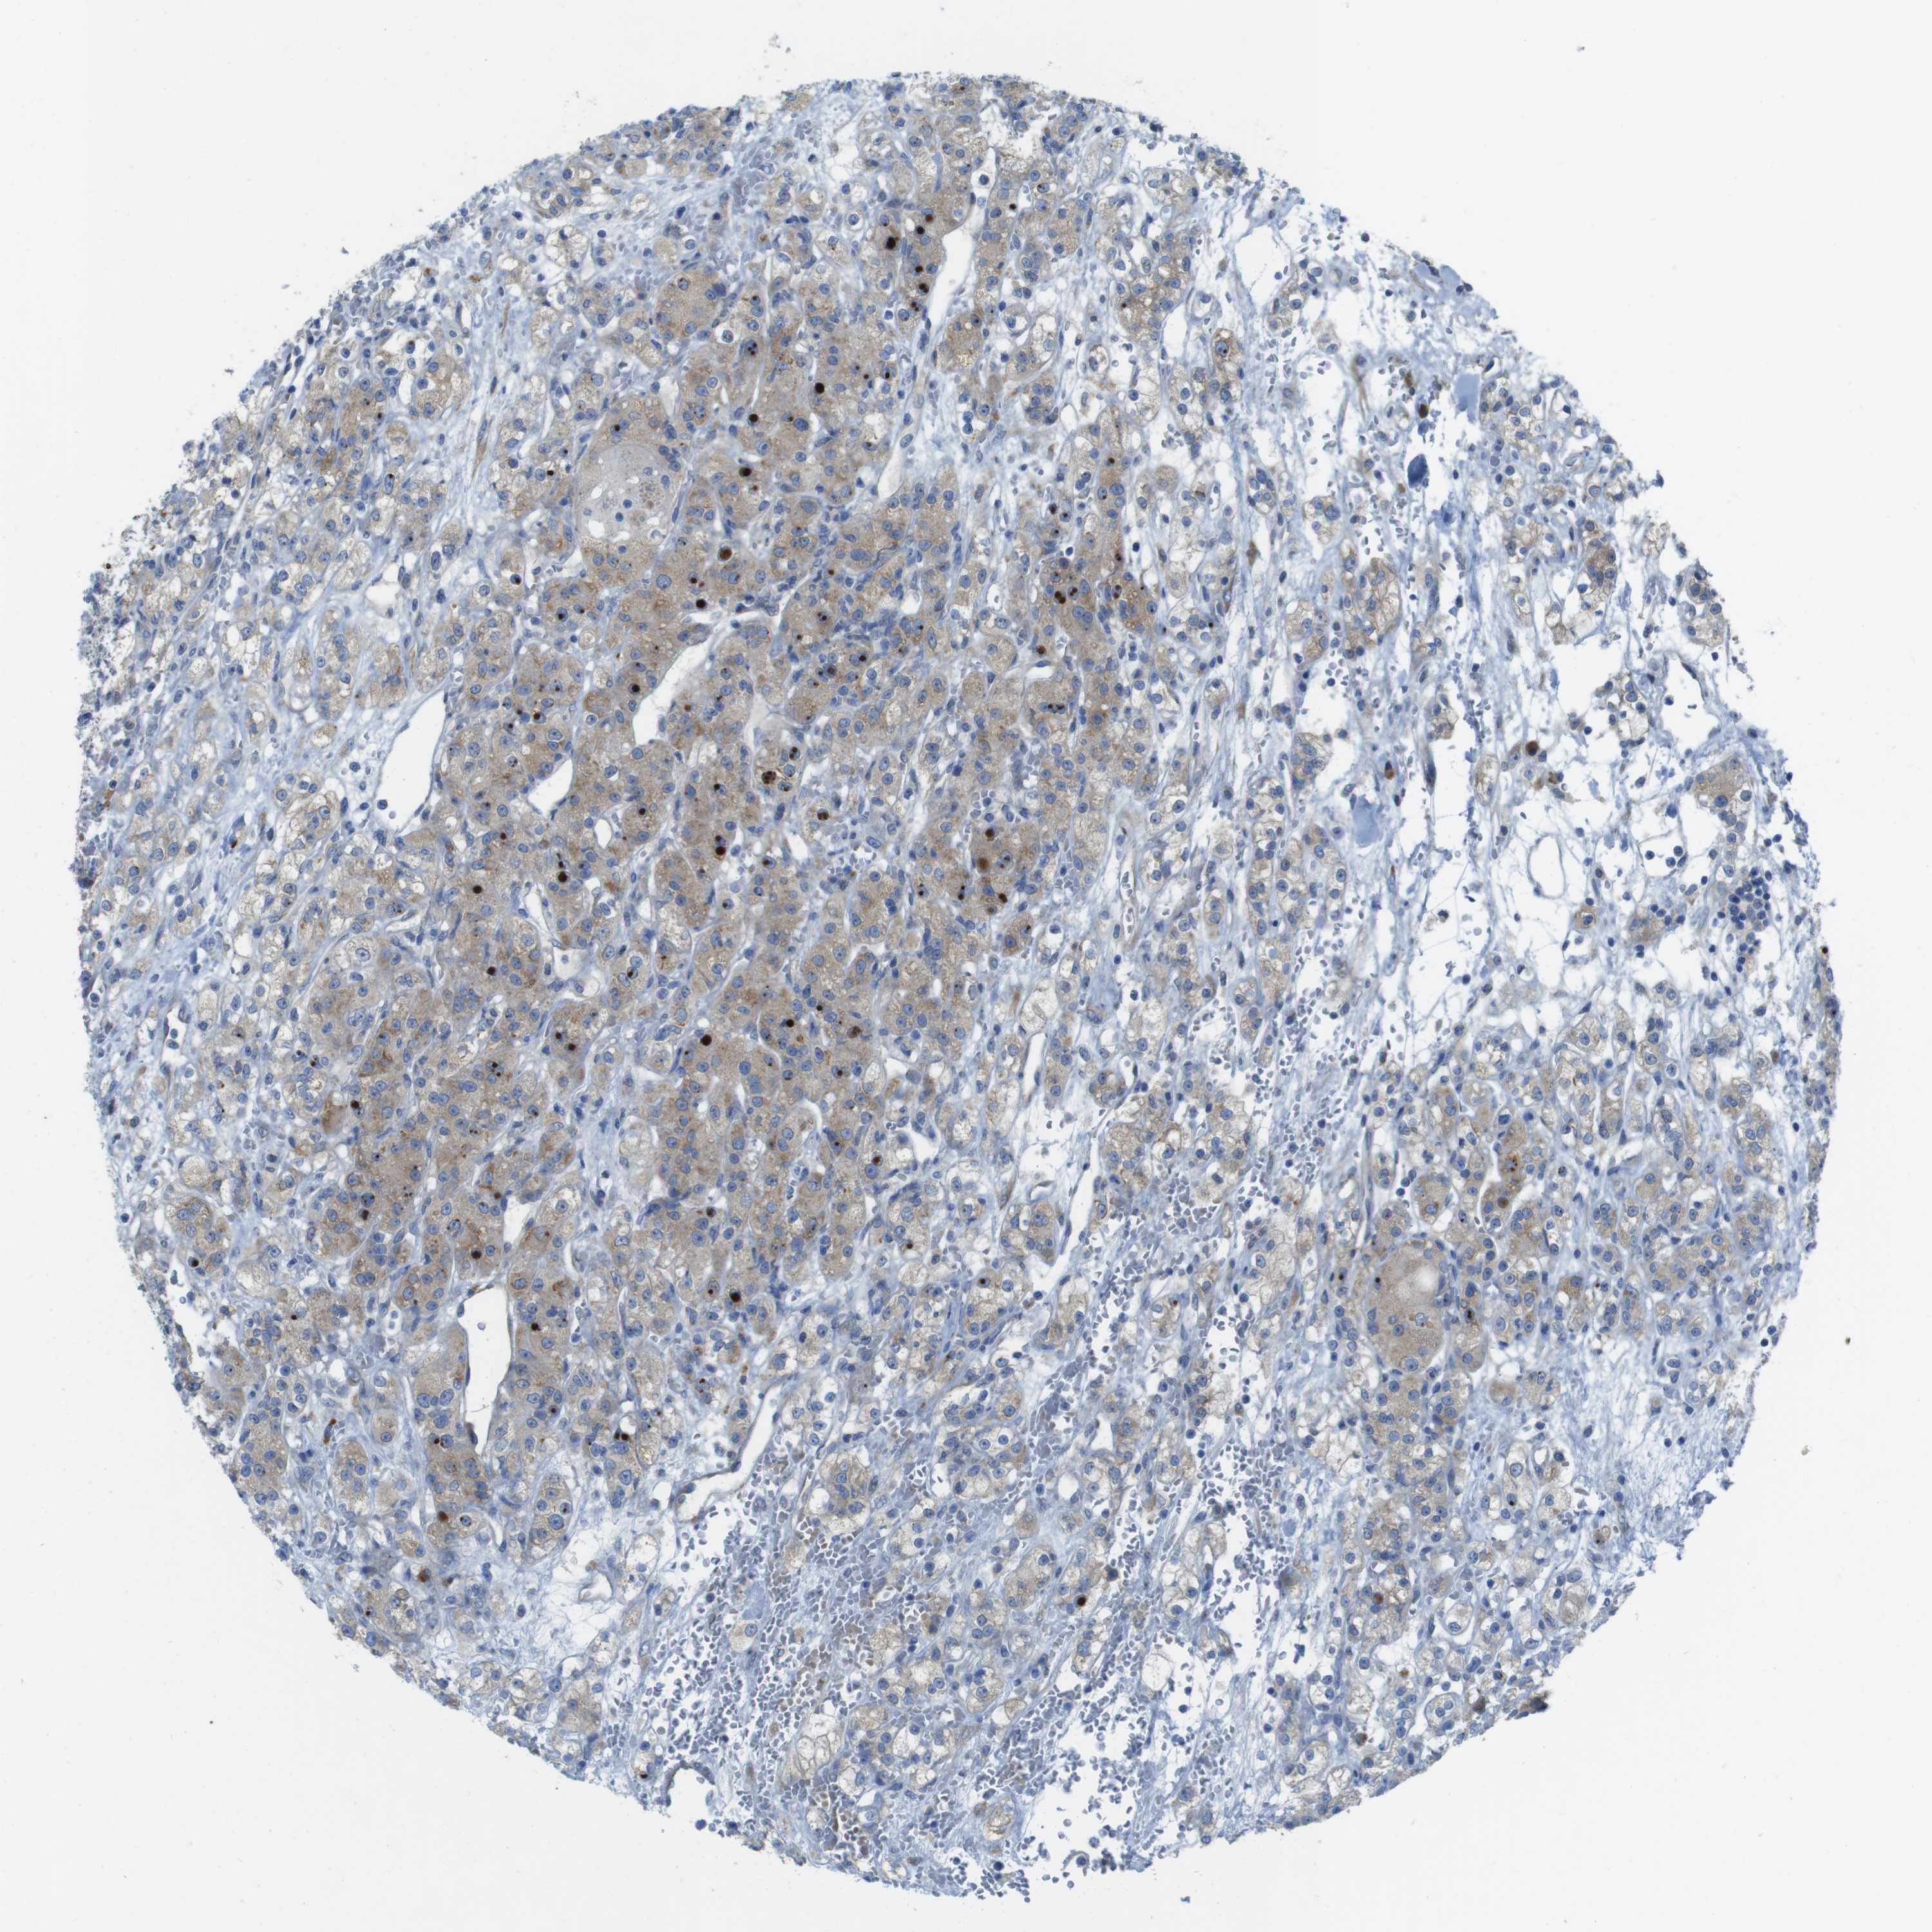

KICH TCGA KIRC TCGA KIRC VALIDATION KIRP TCGA PROTEIN RCC CPTAC PROTEIN EXPRESSION

Renal cancer

Kidney renal clear cell carcinoma

KIDNEY RENAL CLEAR CELL CARCINOMA (VALIDATION) - Interactive survival scatter ploti

TMEM234 is not prognostic in Kidney Renal Clear Cell Carcinoma (validation)

Average pTPM 11.5

Number of samples 100